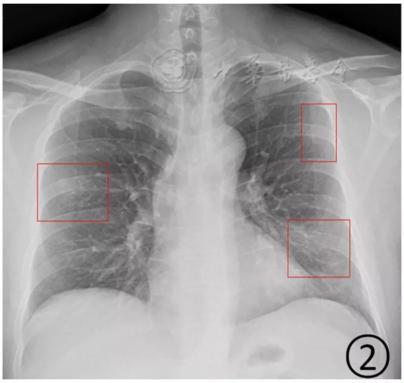

根據感染程度不同,有的僅單側肺出現這種磨玻璃影,還有的雙側都有。磨玻璃影可以累及一個肺葉,也可同時累及多個肺葉。

▲上面的圖:單側肺出現磨玻璃影,累及一個肺葉;下面的圖:雙側肺均出現磨玻璃影,累及多個肺葉(圖片來自網絡)

上海市胸科醫院放射科主任醫師于紅在接受媒體采訪時介紹,新冠肺炎的影像特征與其他病毒性肺炎相似。早期患者肺部多會出現單個或多個小斑片影、局灶性磨玻璃影等。隨著病情進展,病灶增多并融合,范圍擴大,多個肺葉出現小斑片,或者表現為彌漫性磨玻璃影及實變結節影。